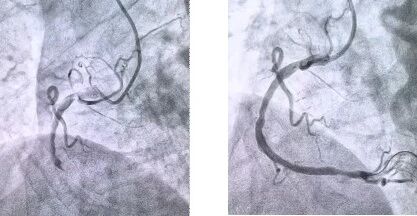

患者抵達醫(yī)院后,簡化掛號、繳費等中間環(huán)節(jié),迅速溝通病情,需要緊急介入治療,獲得家屬同意,立即送至導管室。造影顯示其右冠狀動脈中段完全閉塞,醫(yī)生迅速實施血栓抽吸,球囊擴張和藥物洗脫支架植入術。36 分鐘后,閉塞血管恢復正常血流,吳大爺?shù)难獕骸⑿穆手饾u平穩(wěn),胸痛癥狀明顯緩解。術后三天,他便轉(zhuǎn)入普通病房進行康復訓練,重拾健康生活。